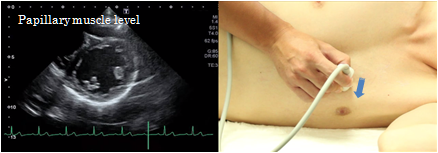

Papillary muscle level

At the papillary muscle level of the short axis view of the left ventricle, the anterior papillary muscle is shown on the right side of the screen and the posterior papillary muscle on the left side. The image of the left ventricle should form a perfect circle. This view is primarily used for the evaluation of wall motion abnormalities.